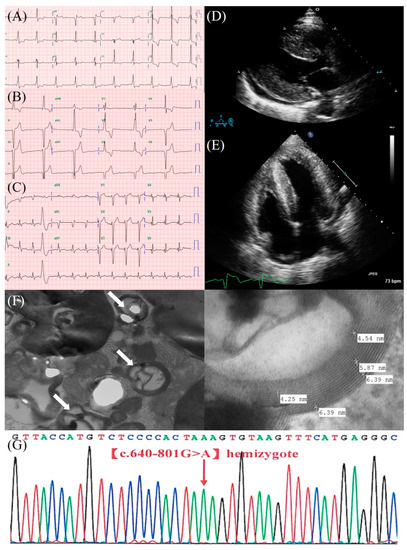

| 2008 | 63 | Palpitation | ECG: Sinus rhythm, ventricular preexcitation, LVH (Figure 1A) Holter: Normal TTE: Concentric LVH, impaired LV relaxation (Figure 1D,E) | OPD follow-up |

| 2016 | 71 | Dizziness | ECG: 3:1 AV block (Figure 1B) | PPM (DDDR), OPD follow-up |

| 2021 | 76 | Aggravated DOE | ECG: Ventricular pacing rhythm, QRS = 200 ms ECG (s/p CRT): Biventricular pacing rhythm, QRS = 160 ms (Figure 1C) TTE: Concentric LVH, large apical LV akinesis, impaired LV systolic function, LVEF = 20%, E/e′: 21.4, LV mass index: 160.0 g/m2 TTE (s/p CRT): Concentric LVH, apical LV hypokinesis, LVEF = 35%, E/e′: 11.9, LV mass index: 214.5 g/m2 | CRT, HF drugs, ERT, OPD follow-up |

| Endomyocardial biopsy | Cardiomyocytes are focally vacuolated with a lace-like appearance. The electron microscope showed laminated lysosomal inclusions (zebra bodies) (Figure 1F). | Compatible with FD |

| Genetic sequencing | Genotype: c.640-801G>A (Figure 1G) | Also known as IVS4+919G>A and c.936+919G>A, Cardiac variant of FD [7] |